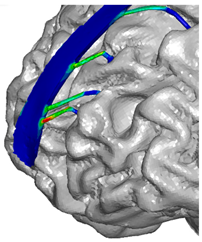

| Frontal veins |  |  |  |

| Parietal veins |  |  | |

| Occipital veins |  |  |